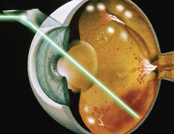

嚴格控制血糖、血壓、血脂和定期做眼科檢查對保護視力非常重要。一旦發現眼內有新生血管生長,或者黃斑點附近有水腫和滲漏,便須要安排眼內注射抗血管內皮生長因子或激光治療,以保存視力。假如患者情況嚴重,如視網膜脫落、眼內出血或持續黃斑水腫,玻璃體切除手術就能助其恢復視力。

![]() 糖尿病視網膜激光治療 |